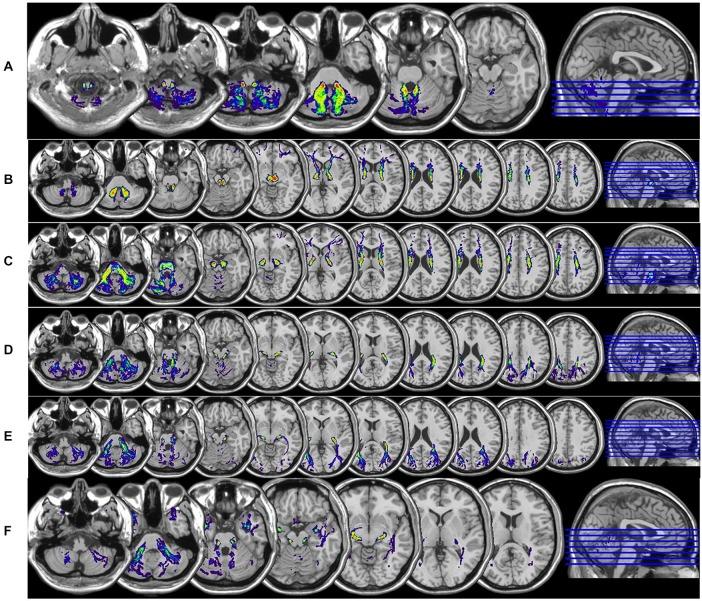

Cerebellar white matter (WM) connections to the central nervous system are classified functionally into the Spinocerebellar (SC), vestibulocerebellar (VC), and cerebrocerebellar subdivisions. The SC pathways project from spinal cord to cerebellum, whereas the VC pathways project from vestibular organs of the inner ear. Cerebrocerebellar connections are composed of feed forward and feedback connections between cerebrum and cerebellum including the cortico-ponto-cerebellar (CPC) pathways being of cortical origin and the dentate-rubro-thalamo-cortical (DRTC) pathway being of cerebellar origin. In this study we systematically quantified the whole cerebellar system connections using diffusion tensor magnetic resonance imaging (DT-MRI). Ten right-handed healthy subjects (7 males and 3 females, age range 20-51 years) were studied. DT-MRI data were acquired with a voxel size = 2 mm × 2 mm × 2 mm at a 3.0 Tesla clinical MRI scanner. The DT-MRI data were prepared and analyzed using anatomically-guided deterministic tractography methods to reconstruct the SC, DRTC, fronto-ponto-cerebellar (FPC), parieto-ponto-cerebellar (PPC), temporo-ponto-cerebellar (TPC) and occipito-ponto-cerebellar (OPC). The DTI-attributes or the cerebellar tracts along with their cortical representation (Brodmann areas) were presented in standard Montréal Neurological Institute space. All cerebellar tract volumes were quantified and correlated with volumes of cerebral cortical, subcortical gray matter (GM), cerebral WM and cerebellar GM, and cerebellar WM. On our healthy cohort, the ratio of total cerebellar GM-to-WM was ~3.29 ± 0.24, whereas the ratio of cerebral GM-to-WM was approximately 1.10 ± 0.11. The sum of all cerebellar tract volumes is ~25.8 ± 7.3 mL, or a percentage of 1.6 ± 0.45 of the total intracranial volume (ICV).

小脑白质(WM)与中枢神经系统的连接在功能上可分为脊髓小脑(SC)、前庭小脑(VC)和大脑小脑亚区。脊髓小脑通路从脊髓投射至小脑,而前庭小脑通路则从内耳的前庭器官投射而来。大脑小脑连接由大脑和小脑之间的前馈和反馈连接组成,包括起源于皮质的皮质 - 脑桥 - 小脑(CPC)通路以及起源于小脑的齿状核 - 红核 - 丘脑 - 皮质(DRTC)通路。在本研究中,我们使用扩散张量磁共振成像(DT - MRI)系统地量化了整个小脑系统的连接。研究了10名右利手健康受试者(7名男性和3名女性,年龄范围20 - 51岁)。DT - MRI数据在3.0特斯拉临床MRI扫描仪上以体素大小 = 2毫米×2毫米×2毫米采集。使用解剖学引导的确定性纤维束成像方法对DT - MRI数据进行处理和分析,以重建脊髓小脑、齿状核 - 红核 - 丘脑 - 皮质、额脑桥小脑(FPC)、顶脑桥小脑(PPC)、颞脑桥小脑(TPC)和枕脑桥小脑(OPC)。DTI属性或小脑纤维束及其皮质代表区(布罗德曼区)以标准的蒙特利尔神经病学研究所空间呈现。对所有小脑纤维束体积进行量化,并与大脑皮质、皮质下灰质(GM)、大脑白质以及小脑灰质和小脑白质的体积进行相关性分析。在我们的健康队列中,小脑灰质与白质的总体积比约为3.29±0.24,而大脑灰质与白质的体积比约为1.10±0.11。所有小脑纤维束体积的总和约为25.8±7.3毫升,占总颅内体积(ICV)的1.6±0.45%。